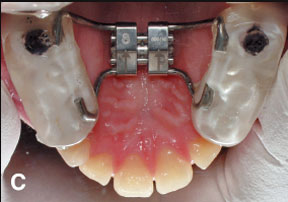

Enter the non-helix, a comfortable “non-food-catcher” appliance constructed from .036" round beta titanium wire (Fig. 1). The lateral expansion arms of the appliance are adapted to the lingual aspects of the dentition (Fig. 2). The palatal portion is bent over the lateral arms and then rounded anteriorly to fit the shape of the arch, just lingual to the anterior teeth.

Fig. 1 Non-helix appliance adjusted for molar rotation, “fan expansion,” and distal movement of upper right first molar. Archwire extended to upper left first molar to prevent rotation, but cut short of upper right first molar to allow distal movement.